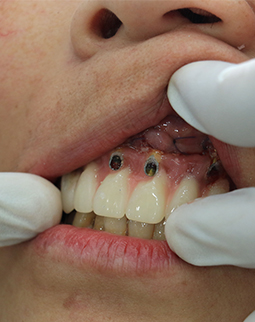

在香港找了很多的口腔诊所,都说我的牙齿“病入膏肓”,要治疗的话只能全部拔掉种植,香港的消费实在很贵,所以我决定到深圳看看。好在遇到了深圳口碑比较好的口腔医院,他们帮我拆除了烤瓷牙冠,经过系列严苛检查,很耐心的跟我沟通牙齿问题,牙周炎症、蛀牙、牙髓炎等问题让我的牙齿已走到了末路,这被烤瓷牙吞噬的健康与口福,只能通过拔牙再种牙的方式来解决了。

今天要做的第一件事,就是把半口的烤瓷牙冠全部拆掉,然后做了洗牙和局部上药消炎,等炎症控制好了以后,再说拔牙和种牙,医生跟我说,如果牙周炎症不做处理,口内的细菌太多拔牙后会出现感染,洁牙的过程很舒服,洁牙师和助理搭配,洗的很细心。身边不少朋友都担心洁牙会让牙齿变松,我到今天才明白,牙结石是造成我牙周炎症的主要原因,烤瓷牙是导致我根尖周炎的罪魁祸首,哎……强烈建议大家日常的口腔保健,1年两次洁牙还是要做起来的,积极的预防比后期的治疗更重要!洁牙完牙齿会更干净,口气也会清新不少。